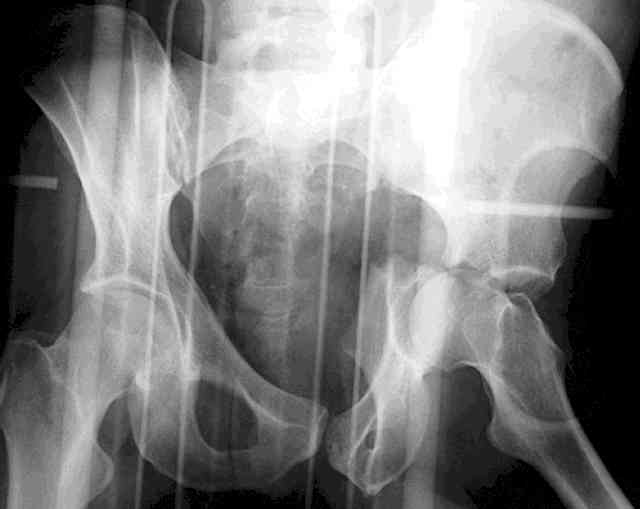

I'll include a few images of a similar injury in a similarly large male patient. This patient "showed up" in our ER c/o hip pain 2 months after being treated in the lateral position, without a quality reduction, without an anterior column transverse supporting implant, with an unbalanced plate applied too medially, with insufficient caudal segment fixation...it took over 8 hours and a 3+ l blood loss to debride the callus from front then

back, excise the HO, release his sciatic nerve, reduce the head-transverse-wall, and fix it...and now it's a staging procedure.

The 2nd example is of a motorcyclist with a transverse fracture-dislocation...he had a closed attempted reduction and placed in traction but the manipulative reduction was not concentric (not unusual for this injury pattern)...so the traction was adjusted to be just enough to disengage the head from the fracture (12#) until he could be cleared for surgery one day after injury...he was treated "urgently" then with a prone KL, clean the fracture, reduce and clamp it, screw it, support with a balanced plate, close, and enjoy...2-3hours, 400cc EBL, blah, blah, blah..